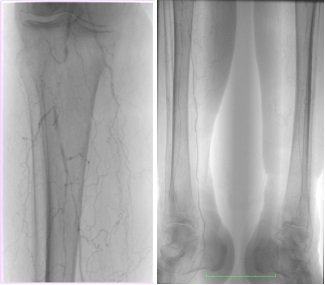

Arteriografía:

1.- Poplítea con estenosis focal significativa en tercera porción y obstrucción de 3 cm. en el tronco tibio- peroneo.

2.- Los troncos distales permeables, la tibial posterior y peronea en todo su trayecto. (Fig. 3)

Fig. 3. Arteriografía